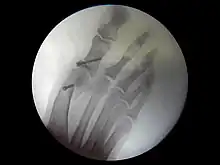

Bilan radiographique

Le diagnostic est avant tout clinique, mais des radiographies sont indispensables pour mesurer la déformation et adapter la technique chirurgicale aux spécificités du patient. Les radiographies doivent être effectuées de façon rigoureuse : clichés d'avant-pied de face, profil, et 3/4, patient debout en charge. Ce dernier critère est indispensable car le squelette du pied adopte des positions dans l'espace qui diffèrent selon que le poids du corps repose ou non sur lui. C'est l'état du squelette debout en charge qui doit guider le geste chirurgical.

Du point de vue de la technique pure, l'opération peut être menée selon plusieurs modalités :

- chirurgie classique : le chirurgien incise la peau en regard des zones à traiter ;

- chirurgie mini-invasive[7] : les techniques sont adaptés pour permettre d'effectuer les mêmes gestes, mais par des incisions (et donc des cicatrices) plus petites et en préservant mieux les tissus sous-cutanés ;

- chirurgie percutanée[8] : les avancées techniques les plus récentes permettent de pratiquer les gestes chirurgicaux à travers la peau. La taille des incisions ne dépasse alors pas quelques millimètres.